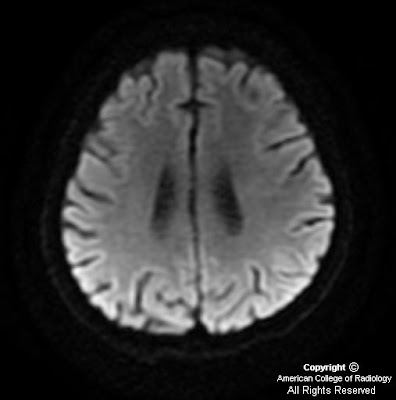

14-year-old child with history of Acute Lymphoblastic Leukemia (ALL), on induction chemotherapy complaining of left sided weakness and facial asymmetry of acute onset.

Diffusion weighted images with corresponding ADC maps show restricted diffusion involving bilateral centrum semiovale (Figure 1 and Figure 2).

High level of adenosine is thought to be responsible for methotrexate induced toxicity. Statistically the periventricular white matter is the most common area affected. On diffusion weighted imaging these areas show increased signal intensity and hypointensity on corresponding apparent diffusion coefficient (ADC) maps. There may be no abnormality identified on T1, T2, and FLAIR sequences during the acute symptomatic phase.